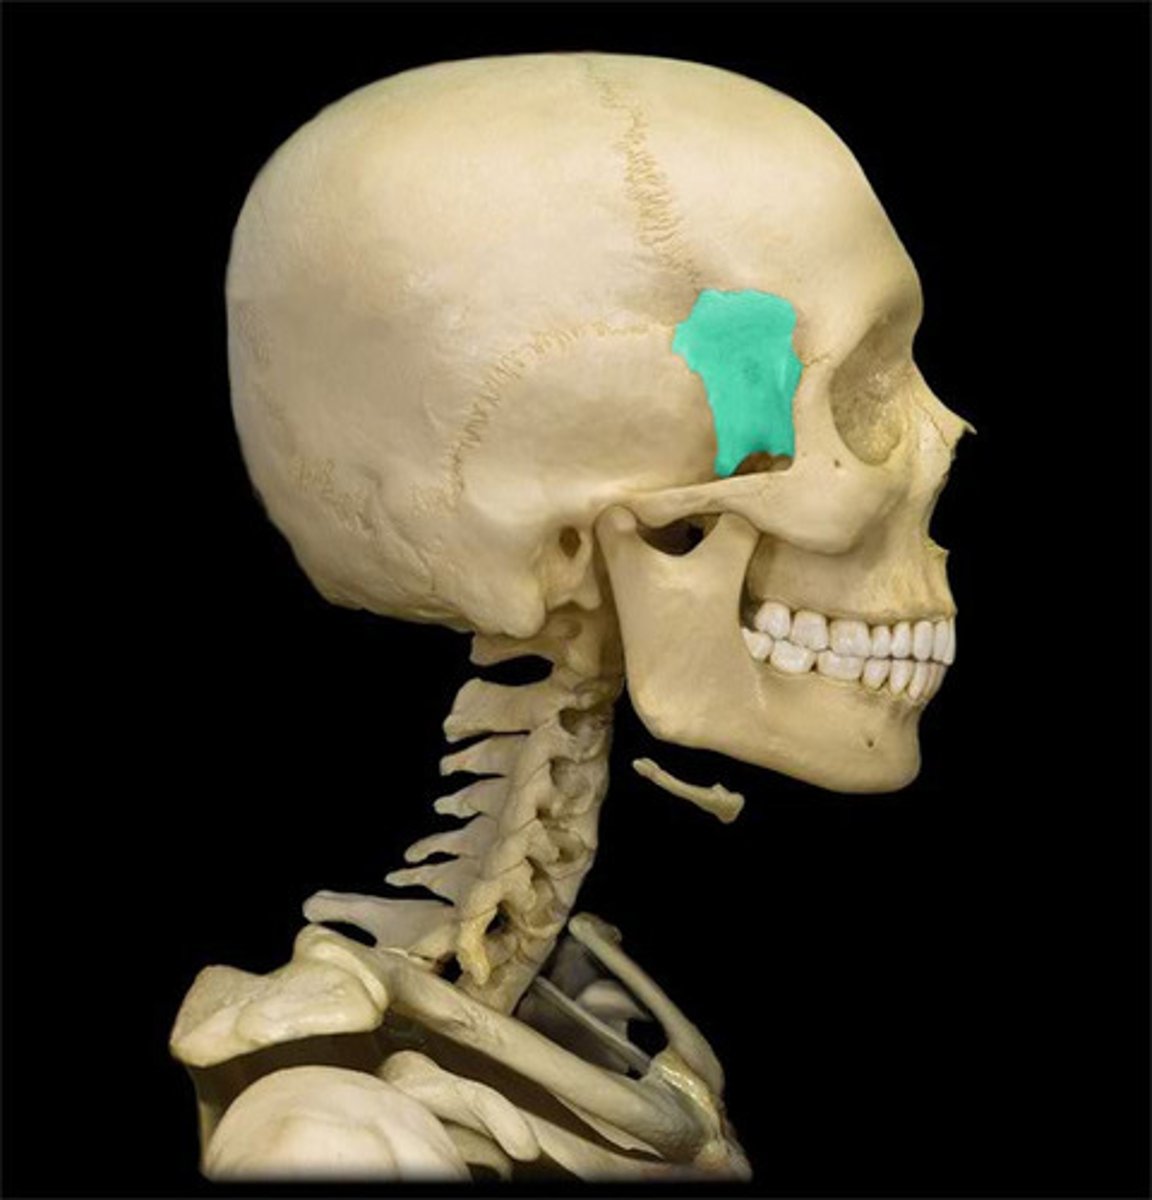

Sphenoid

Sphenoid

Sphenoid

Sphenoid

Lacrimal Bone

Zygomatic Bone

Zygomatic Bone